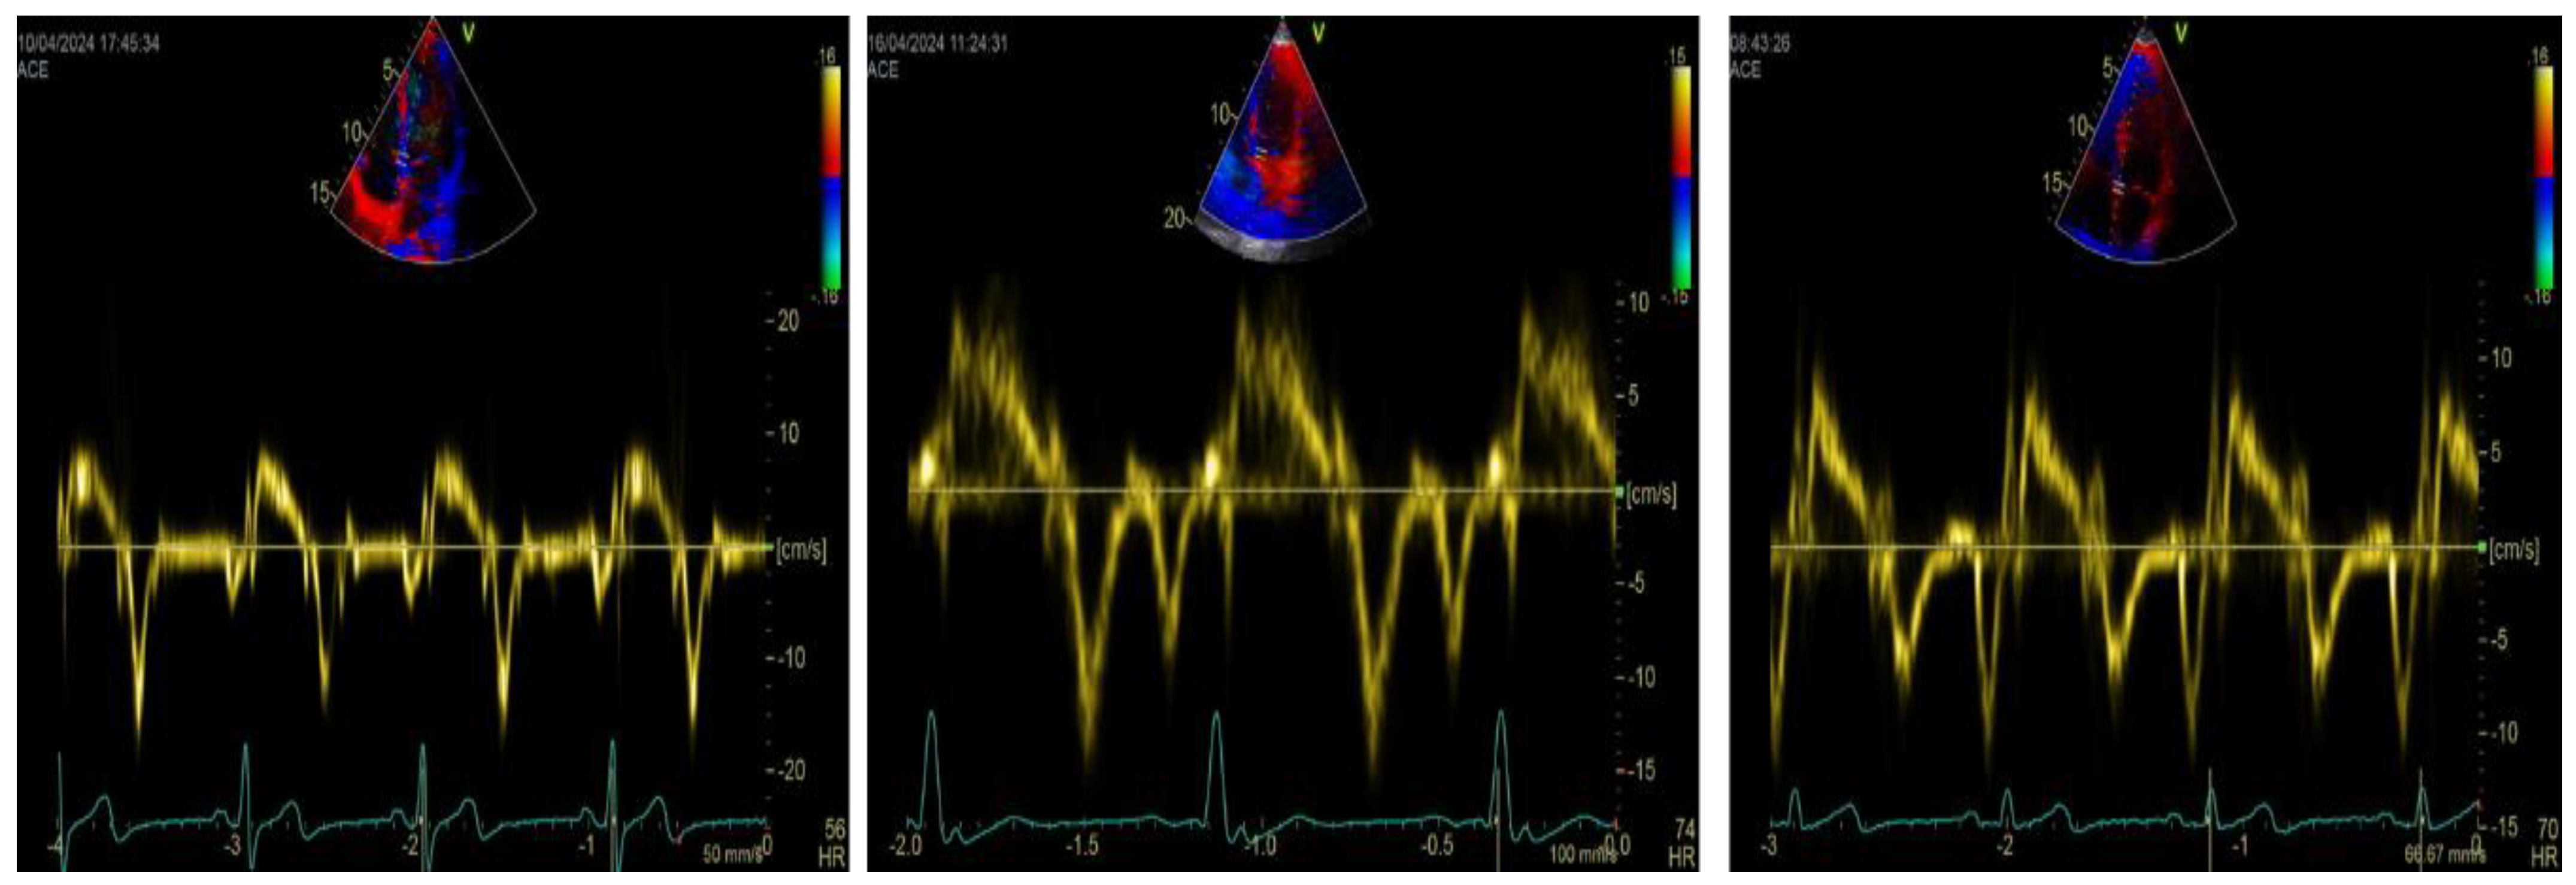

5. Tissue Doppler Imaging and LA Function: A Simplified, Complementary Approach

6. TDI-a’ and Outcome

7. TDI-a’ Integrated Echocardiographic Indices